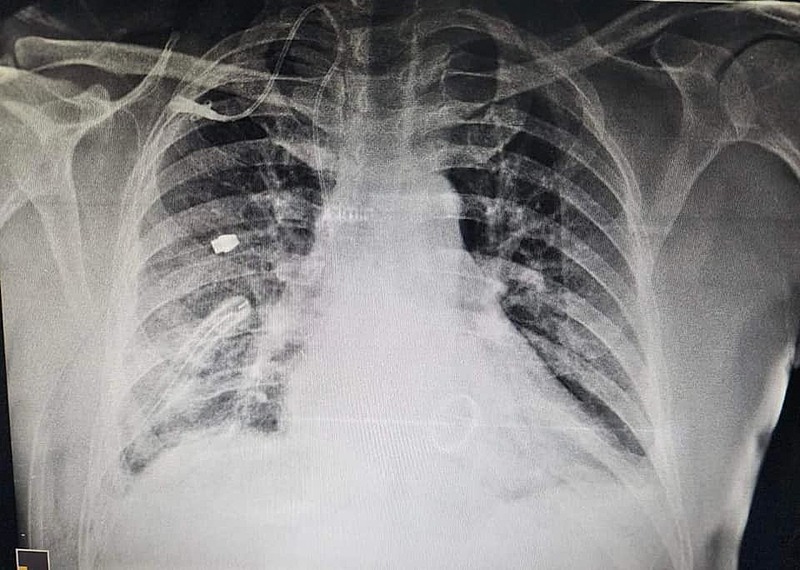

بەڕێوەبەرایەتیی گشتیی تەندروستیی سلێمانی رایدەگەیەنێت لە نەخۆشخانەی پسپۆڕییەکانی دڵ لە شاری سلێمانی توانرا بە شێوازێکی نوێ نشتەرگەریی گۆڕینی زمانەکانی دڵ ئەنجامبدرێت.

ئەمڕۆ شەممە 24ی حوزەیرانی 2023 بەڕێوەبەرایەتیی گشتیی تەندروستیی سلێمانی رایگەیاند "لە نەخۆشخانەی پسپۆڕییەکانی دڵ لە شاری سلێمانی توانرا لەلایەن دکتۆر عەلا سوبحی و ستافی پزیشکان و کارمەندانی بەشی نەشتەرگەرییەوە لە نەخۆشخانەکە نەشتەرگەریی گۆڕینی زمانەی دڵ بە شێوازێکی نوێ ئەنجام بدرێت".

باسی لەوەشکردووە "ئەم نەشتەرگەرییە شێوازێکی پێشکەوتووە و شوێنی برینی نەشتەرگەرییەکەش لەسەر سنگی نەخۆشکە نامێنێتەوە، کەمترین بەش لە تەنیشتی لای راستی نەخۆشەکە دەکرێتەوە".

ئەوەشی خستەڕوو "دوای نەشتەرگەریی توانرا دوای تەنها سێ کاتژمێر بۆری هەناسەی دەستکردی بۆ لاببرێت و دوای رۆژێکیش نێردرا بۆ بەشی چاودێری ئاسایی".

تەندروستی سلێمانی وتوشیەتی "دوای سێ رۆژ لە ئەنجامدانی نەشتەرگەرییەکە نەخۆشەکە بە تەندروستییەکی باشەوە نێردرایەوە بۆ ماڵەوە".